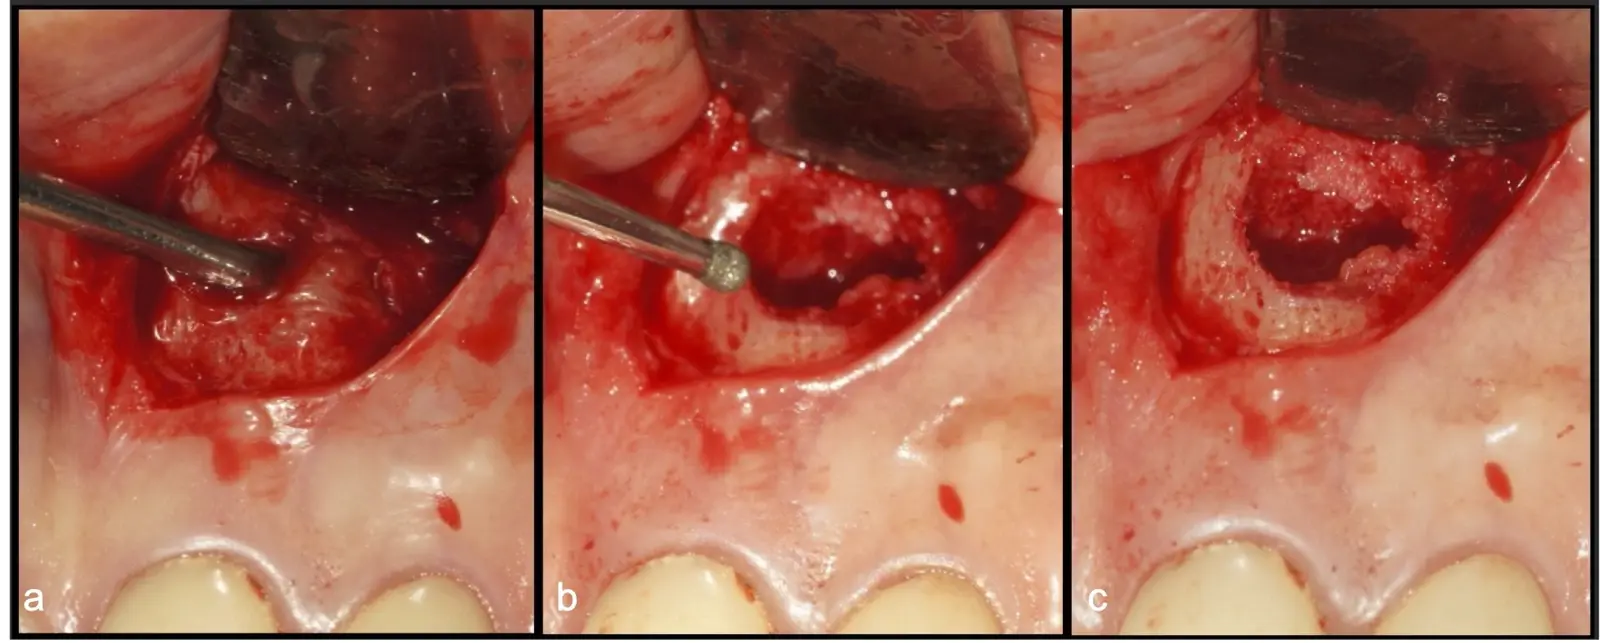

El procedimiento se inicia colocando anestesia y elevando un colgajo mucoperióstico a espesor completo3 (incisión semilunar o intrasurcular con/sin protección papilar) y exponiendo la zona. En seguida se realiza la enucleación de la lesión, eliminando16 o creando una ventana17 en la lámina cortical que contiene el área del ápice; este retiro óseo se realiza con los insertos de forma aplanada dentada o inserto con cobertura diamantada plano o redondo, recordando ser lo más conservador posible (Figura 5).

Después de realizado el acceso e identificado el ápice, se procede a la limpieza de la zona con instrumentos manuales y/o con insertos diamantados de parte activa angulada para poder eliminar todo el tejido patológico del perímetro radicular apical y del tejido óseo circundante (Figura 6).